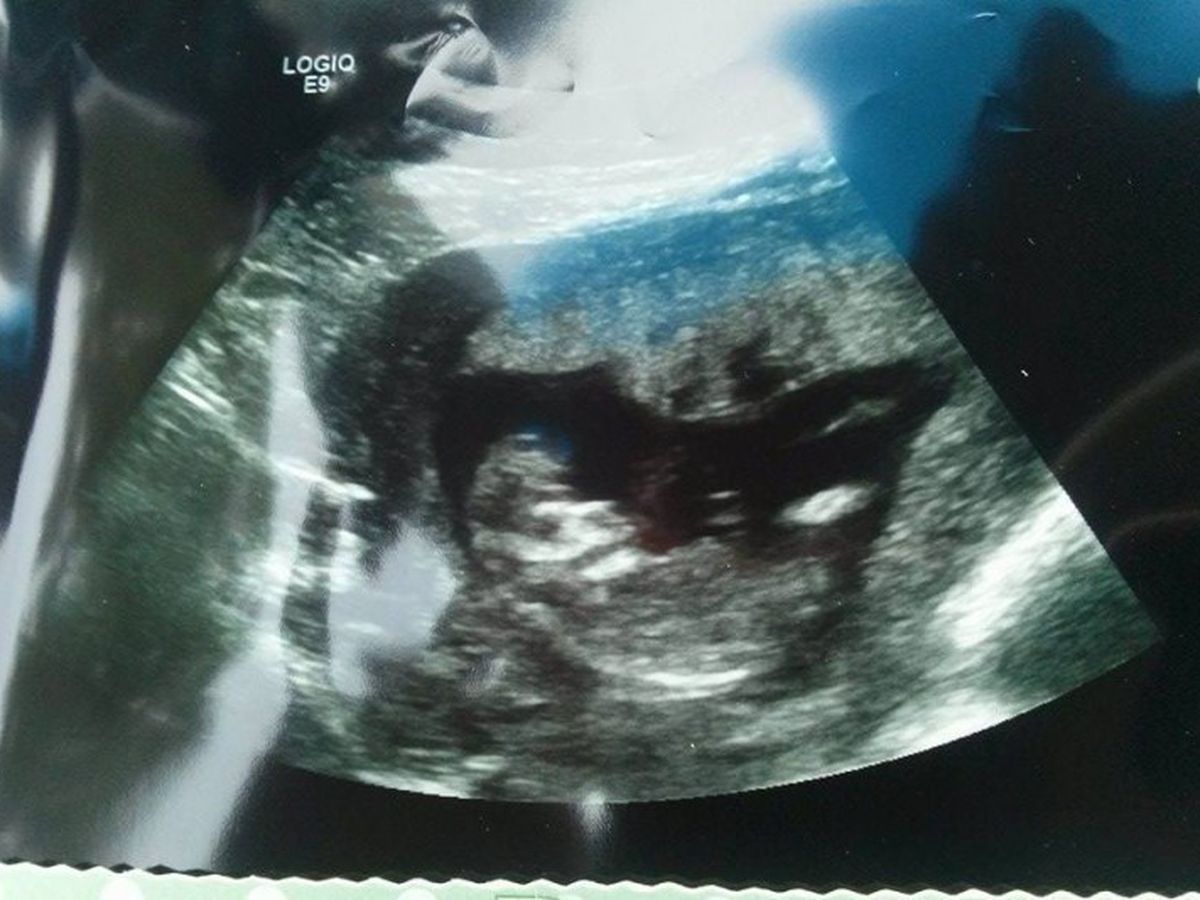

Melody conceived for the 3rd time in June, 2015, and once making it to the 2nd trimester with no issues, we all rejoiced for her. Then tragedy struck at her 14 week ultrasound. Her baby was diagnosed with anencephaly, a serious and terminal birth defect in which a baby is born without parts of the brain and skull. Infants with this disorder survive only a few hours or just a few days after birth in almost all cases.